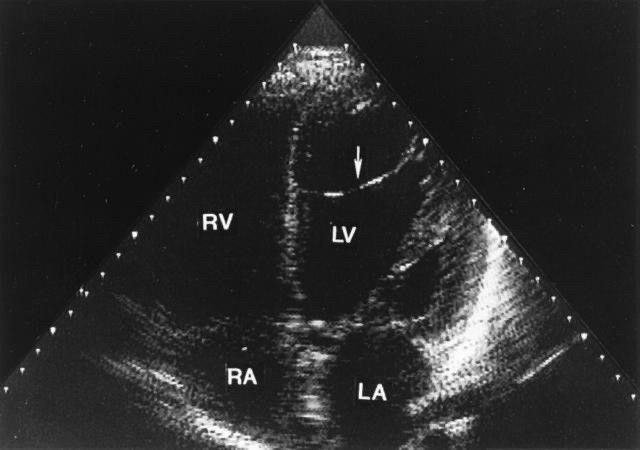

五、左心室假腱索

左心室假腱索可起源于左心室任何一侧壁,多见于前壁和乳头肌,终止于室间隔膜部、肌部或心尖部,少数假腱索起止于乳头肌、心尖部和游离壁之间,极少数位于左心室流出道和主动脉瓣。它一般呈索条状,单条或多条,大致可分为含有和不含有心肌传导组织两大类。既往认为,假腱索可能会因心脏舒缩使其受到机械性牵拉,成为室性早搏的原因。但实际上绝大多数的假腱索没有症状,也没有太大的临床意义。